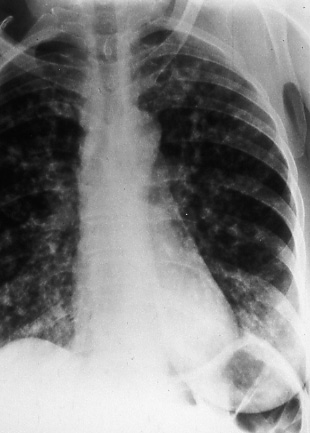

Bronchioalveolar Carcinoma

page 59

Fig. 56: Posterior-anterior radiograph. Bronchioalveolar carcinoma presenting as multiple nodular densities. Note that the edges are not sharply defined, TX N0 M1, stage IV.